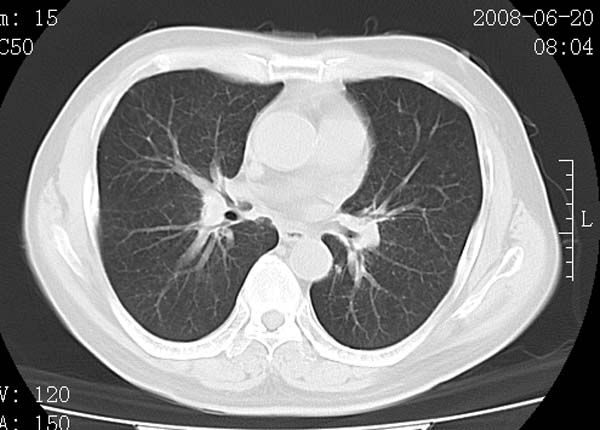

以下是引用守望可可西里在2008-6-24 1:11:00的发言:[br][br] 考虑为周围型肺癌:[br] 1.分叶结节,形态极不规则,蟹足样伸展的恶性浸润特征比较明确。[br] 2.磨玻璃影中由多个更高密度小结节聚集呈梅花瓣样。[br] 3.局部胸膜凹陷征比较明确。[br][br] 另:纵隔胸膜明显增厚、粘连。

以下是引用zjzjr在2008-6-24 11:19:00的发言:[br]支持左下肺周围型肺癌伴右肺转移,纵隔淋巴结转移,心包积液.

以下是引用zhangling在2008-6-24 14:56:00的发言:[br]我们科室意见报告为[br][br]1考虑左下肺周围型肺癌[br]2右肺小结节考虑转移瘤,纵隔淋巴结转移[br]3心包积液. [br] 各位老师分析的相当好 谢意[br]